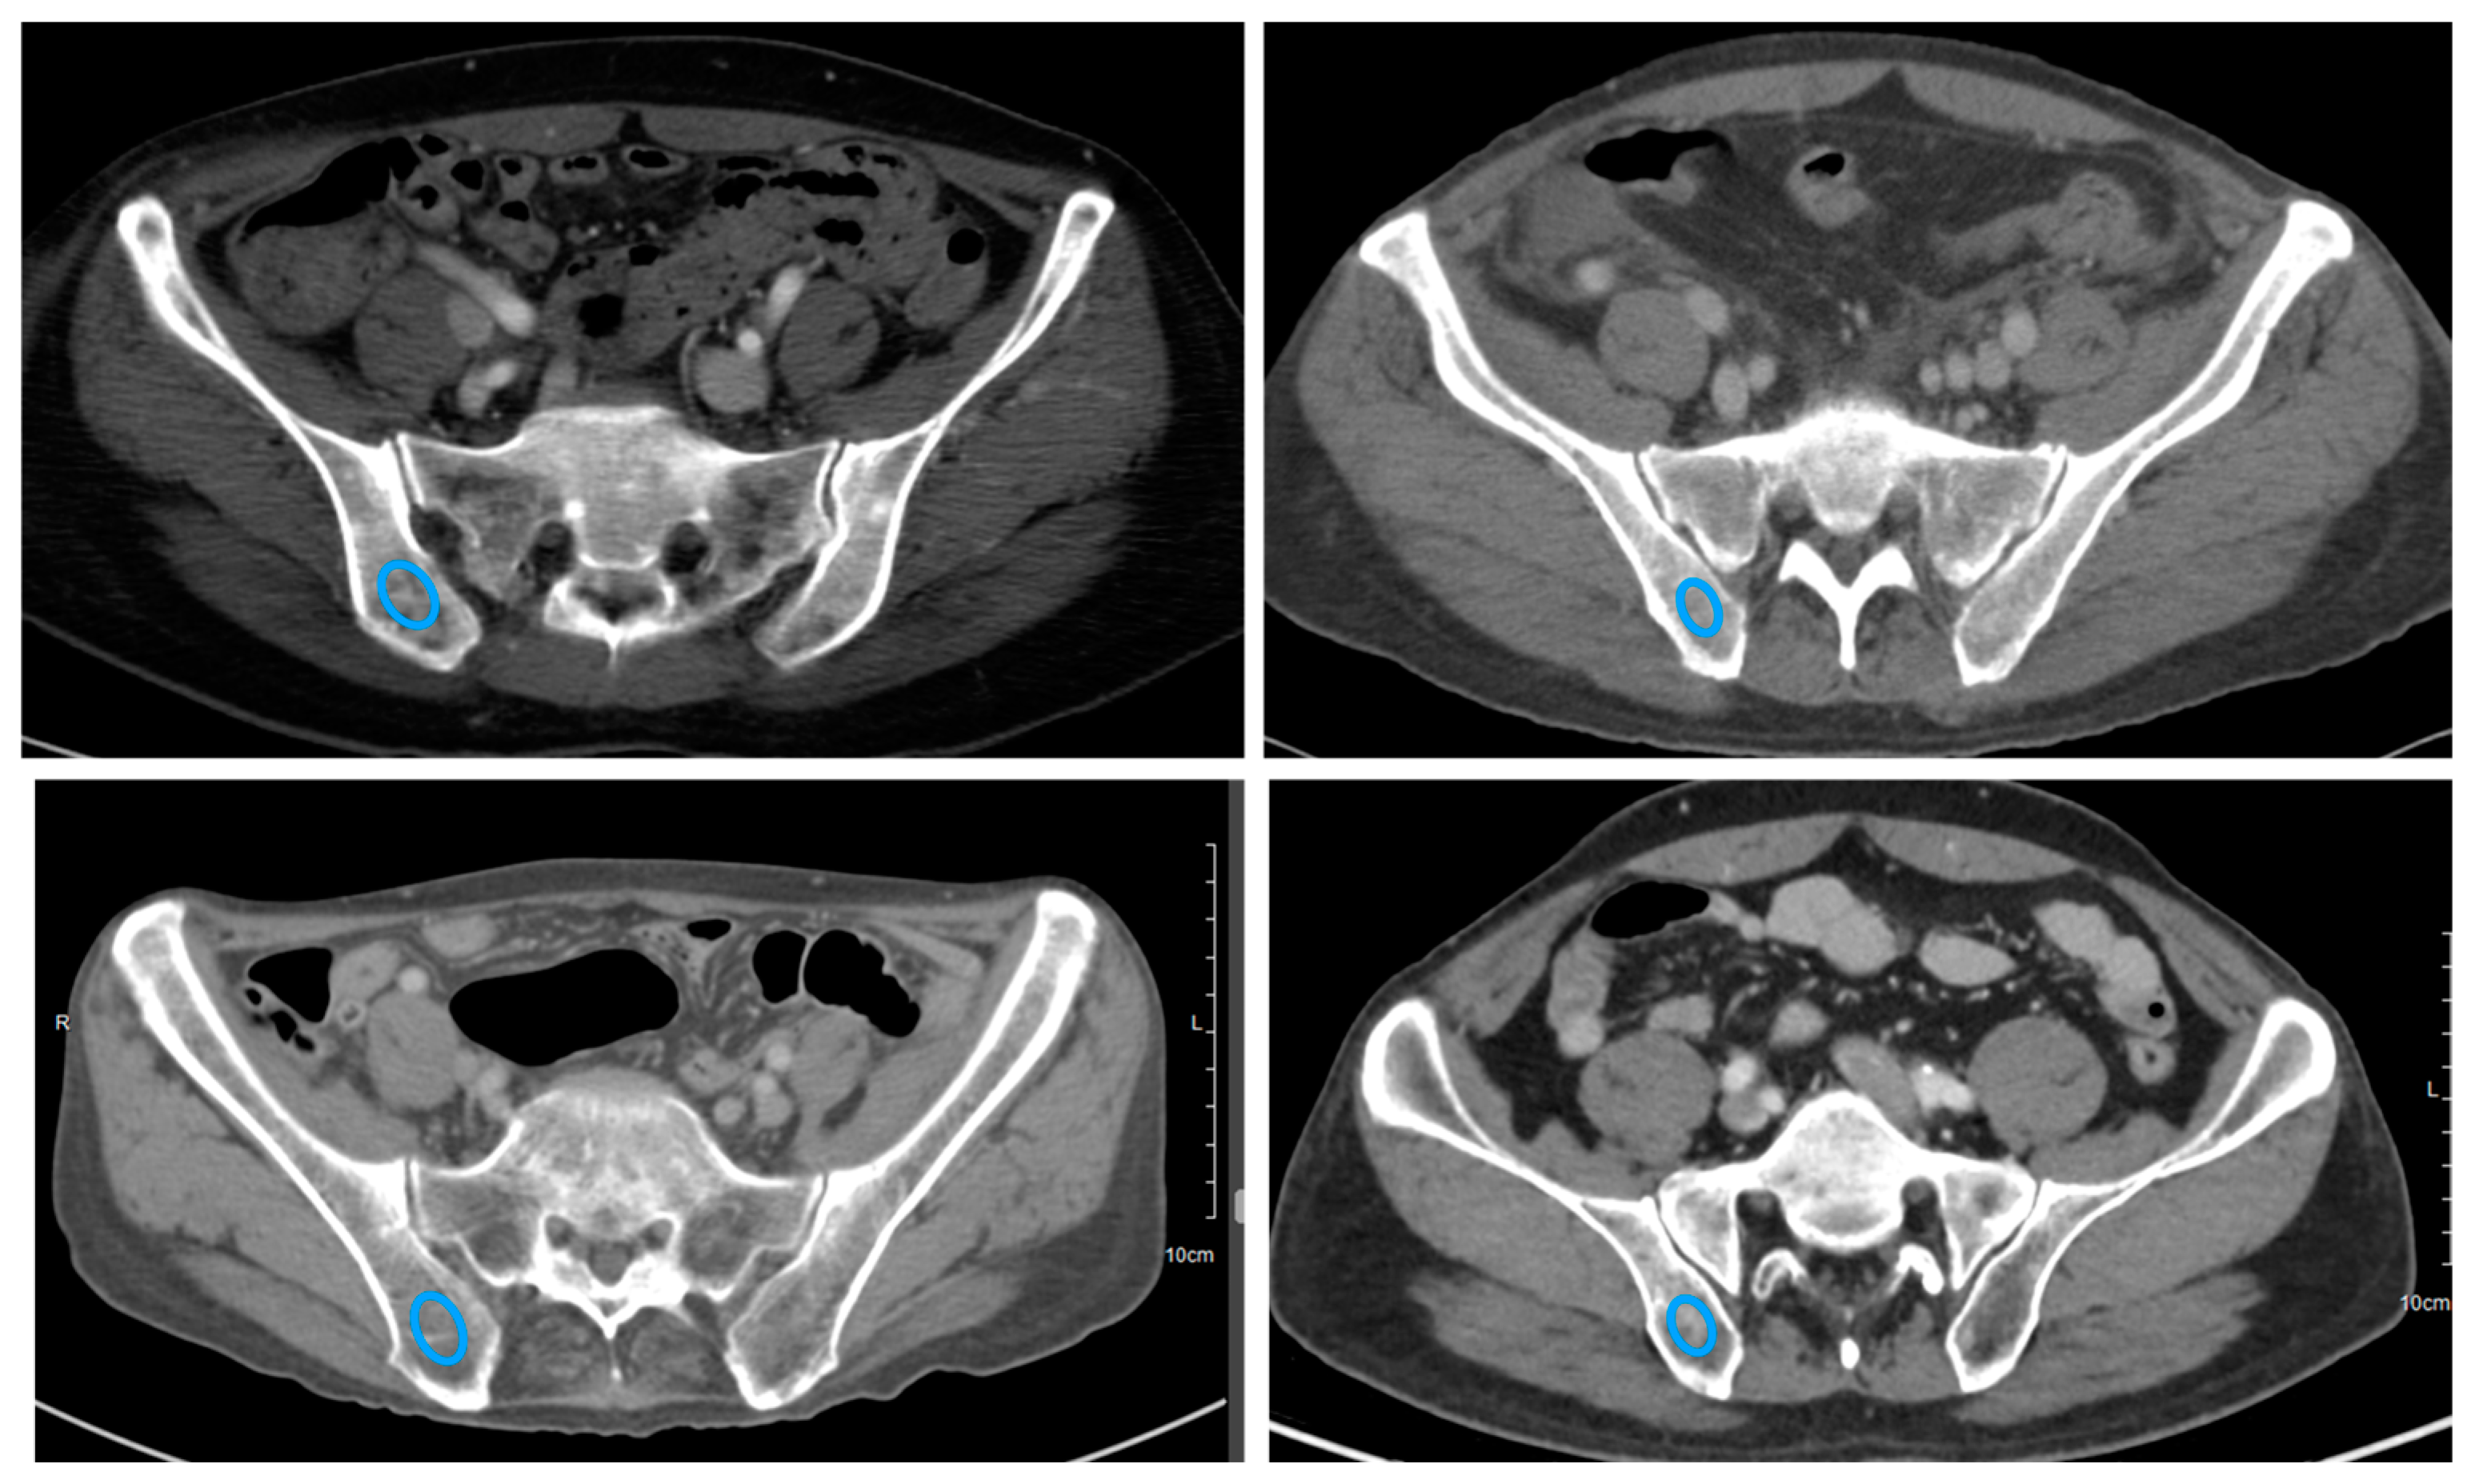

2.3. Assessment of APCT Images

2.4. Region of Interest (ROI) Segmentation, Preprocessing, and Radiomic Feature Extraction

3.2.2. In the Pathology-Positive CT-Negative Group